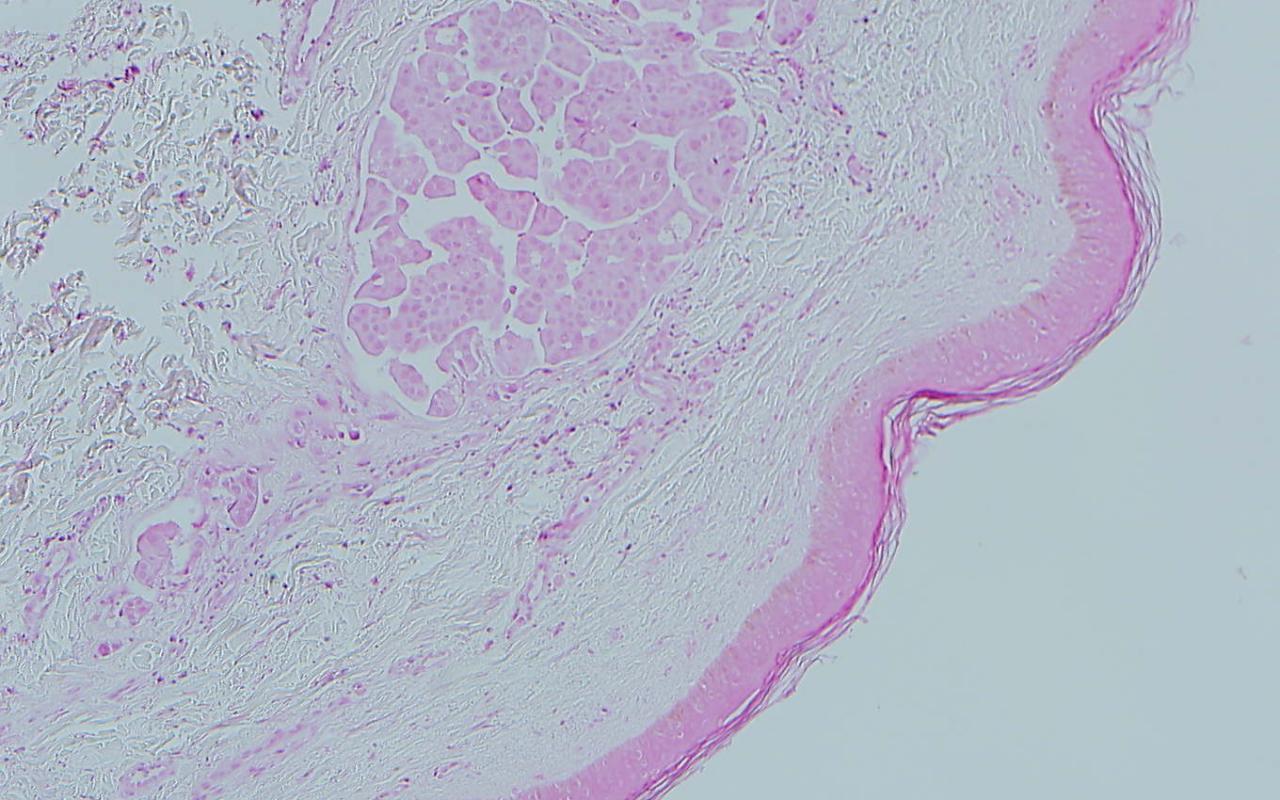

1. Which of the following is the most likely diagnosis of this image?

Correct choice:C. Metastatic adenocarcinoma

Explanation: In this image, the lymphatics are filled with large atypical cells trying to form glands making metastatic adenocarcionma the most likely diagnosis. Merkel cell carcinoma is a sheet of blue cells with salt and pepper nuclei. A lipoma is a collection of normal fat. Melanoma would have nests of atypical melanocytes. A myxoid neurothekeoma would be a loose collection of cells in thekes with a cellular stroma and the cells do not attempt to form glands.